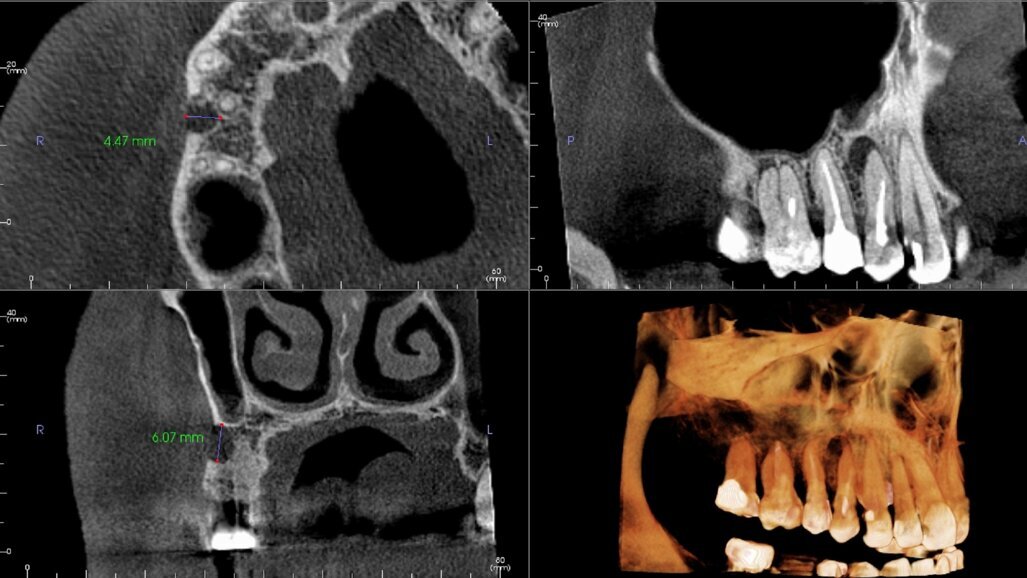

Nieleczone zapalenie przyzębia prowadzi do powstawania ubytków kostnych, które w rezultacie powodują utratę zębów. Tradycyjne metody chirurgicznego leczenia zapalenia przyzębia, takie jak np. autoprzeszczep wykorzystują tkankę kostną dawcy do stymulacji wzrostu nowej kości. Jednak zapewnienie idealnego dopasowania przeszczepu w celu zapobiegania proliferacji tkanek miękkich pozostaje wyzwaniem. Wykorzystanie technologii druku 3D do stworzenia modelu opartego na danych pozyskanych z obrazowania CBCT oferuje obiecujące rozwiązanie. To innowacyjne podejście ma na celu zaprojektowanie modeli dostosowanych do indywidualnych potrzeb pacjenta, przygotowując grunt pod spersonalizowane leczenie zapalenia przyzębia, może mieć także szersze zastosowanie kliniczne.

Proces ten obejmuje dwie kluczowe metody projektowania modeli: jedną dla dostosowanych do indywidualnych potrzeb przeszczepów blokowych ubytków przyzębia i drugą dla dostosowanych przeszczepów blokowych zachowujących zębodół poekstrakcyjny. Znaczenie tych metod polega na personalizacji leczenia z wykorzystaniem danych CBCT do modelowania zębów i kości wyrostka zębodołowego w obszarach z ubytkami przyzębia.

Nowatorski aspekt badania polega na tym, że szczególną uwagę zwrócono na dokładność projektowania modeli i możliwość dostosowania do skomplikowanych defektów kostnych (dzięki wykorzystaniu danych ze skanów CBCT). Badania te torują drogę do przyszłych odkryć i zastosowań klinicznych, w tym do ulepszonych algorytmów segmentacji obrazu, porównań technik druku 3D, wykorzystania materiałów bioresorbowalnych do dostarczania leków oraz testów klinicznych przeszczepów drukowanych w technologii 3D u pacjentów. Istotnym ograniczeniem jest brak możliwości porównania w badaniu dokładności modeli CBCT z warunkami u rzeczywistych pacjentów, co podkreśla potrzebę przyszłej współpracy z badaczami klinicznymi. Oczekuje się, że w miarę ciągłego postępu biotechnologicznego zostaną rozwiązane również wyzwania etyczne i regulacyjne.